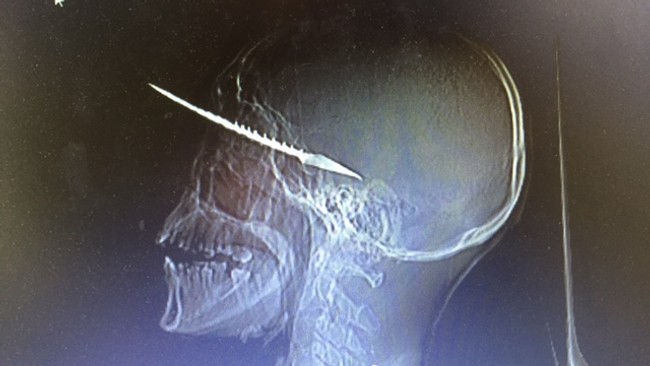

Dag Inge Ulstein slapp eisini at síggja við myndum, hvussu sjúklingar við ógvusligum skaðum í høvdinum, soleiðis sum myndin oman fyri vísir, fingu góða hjálp frá norsku nervaskurðlæknunum.